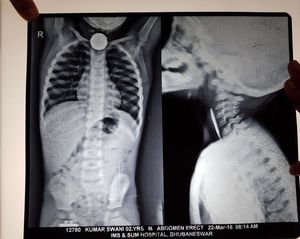

X-ray-Foreign body oesophagus

2YO M child with radio-opaque foreign body in oesophagus...